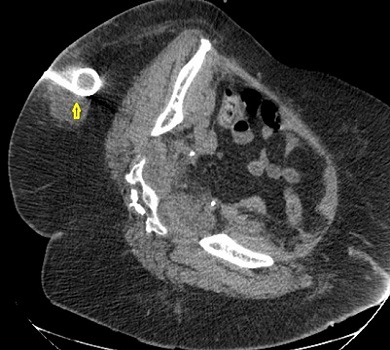

Παρακάτω φαίνονται οι παροχετεύσεις (κίτρινα βέλη) που καταλήγουν εντός των αποστηματικών κοιλοτήτων σε διάφορες τομές της αξονικής τομογραφίας.